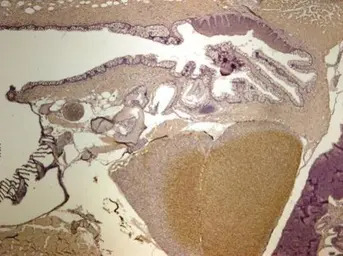

Immunohistochemical analysis of frozen sections of zebrafish retina, using GPI antibody (GTX113203) at 1:2000 dilution.

Immunohistochemical analysis of paraffin-embedded zebrafish tissue, using GPI antibody (GTX113203) at 1:300 dilution.